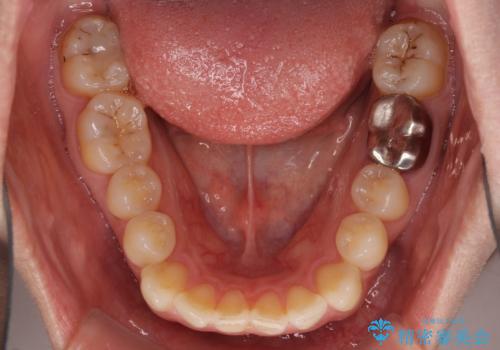

- 唇の閉じにくさを気にして来院された患者様です。

上下左右第一小臼歯4本を抜歯し、ワイヤー装置にて口元を引っ込めるよう矯正治療を行うこととしました。